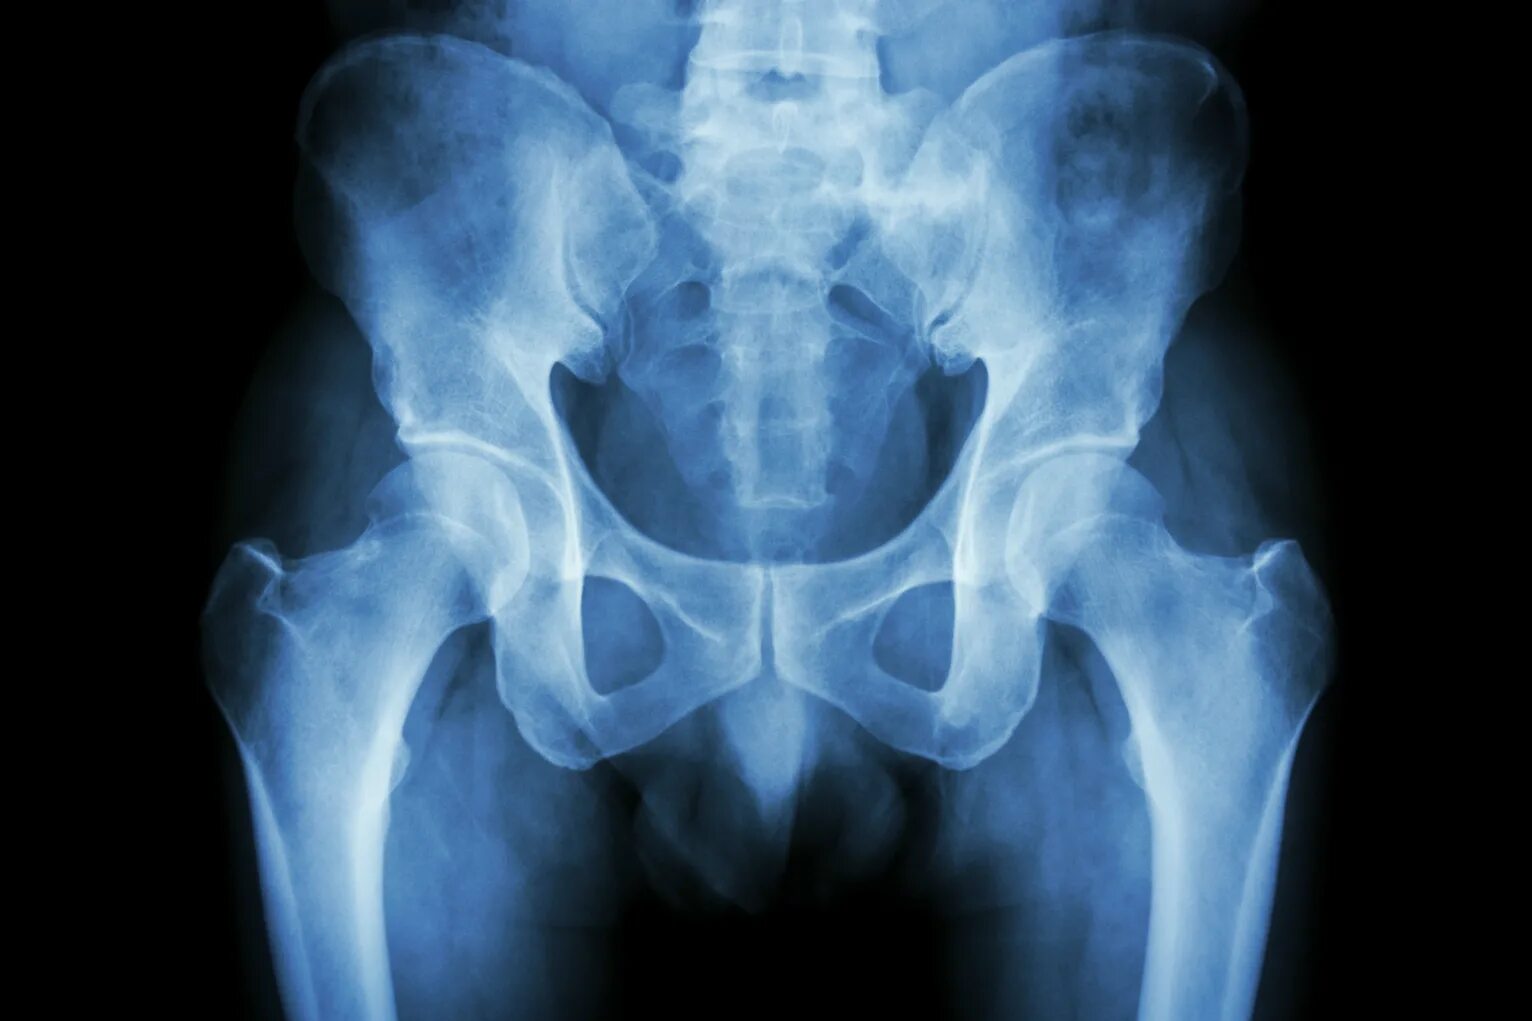

Снимок копчика